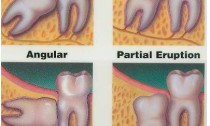

ฟันคุด เป็นลักษณะของฟันกรามแท้โผล่ขึ้นพ้นกระดูกแลพเหงือกมาไม่หมด อาจมาจากหลายๆสาเหตุ เช่น ผลกระทบจากฟันข้างเคียงที่บดบังทำให้ไม่สามารถขึ้นมาได้ เป็นต้น โดยส่วนใหญ่จะเกิดในช่วงอายุ 18-25 ปี

ลักษณะฟันคุด

บางคนอาจอาการบวมที่หน้า

ปวดบวมบริเวณเหงือก

การอักเสบและติดเชื้อ

เป็นฝีในช่องปาก

คราบหินปูนและแบคทีเรียบนฟันและซอกเหงือก

สามารถเกิดการผุได้ง่ายเนื่องจากเป็นอุปสรรคในการทำความสะอาด

การเกิดต่อมน้ำหรือก้อนซีสในเหงือก

โรคเหงือกและขากรรไกรทำไมต้องผ่าฟันคุด

จะทำให้มีอาการเจ็บปวด และมีกลิ่นปาก

ไม่มีประโยชน์ในการใชงาน

มีผลกระทบต่อการสบของฟัน เพราะฟันขึ้นมาไม่สมบรูณ์

เป็นสาเหตุของการเกิดโรคเหงือก หรือสามารถก่อให้เกิดปัญหาโรคเหงือก

ทำให้การทำความสะอาดลำบาก